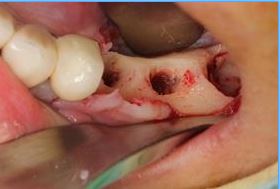

治療前,口內照片;植體外露及牙齦萎縮。

翻開牙肉,可看見植體週圍骨頭嚴重吸收。